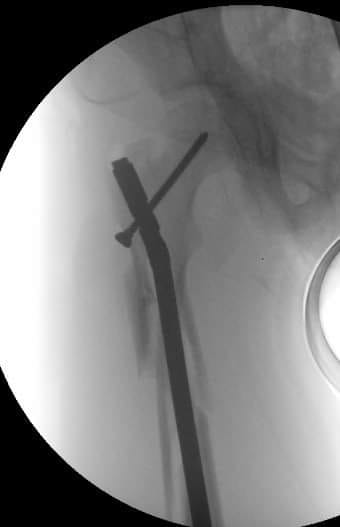

[Ortho] Перелом бедра, девочка 11 лет

Вот, что получилось.

Имя     : 2.jpg